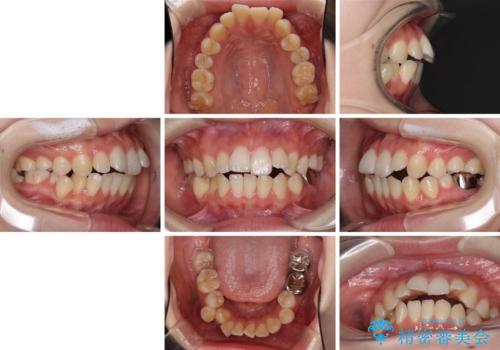

- 口元の突出感を気にして来院された患者様です。

上下左右の第一小臼歯4本を抜歯して口元を下げる治療計画としました。